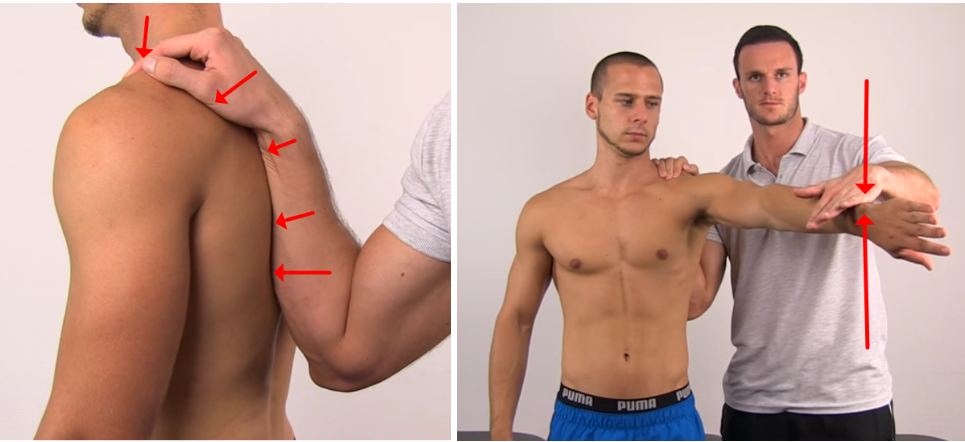

Scapular assistance test

Painful arc가 있는 환자가 왔을 때 한 손으로 견갑골의 내측아래각을 잡은 후 견갑골의 상방회전을 의도적으로 도와주었을 때 통증이 호전되거나 소리가 줄어들면 양성입니다.

양성인 경우에는 견갑골의 안정성이 떨어진것을 의미합니다. 이 검사는 하부 승모근과 전거근의 기능을 도와주는 검사입니다.

Scapular retracction test

Painful arc가 있는 환자가 왔을 때 한손으로 어깨 견갑골 내측연을 아래 사진과 같이 고정시켜주어서 견갑골이 뜨지 않게 고정시켜준 후, Empty can test를 시행했을 때 통증이 감소하게되면 양성입니다.

검사가 양성인 경우에는 견갑골이 뜨지않게 잡아주는 하부승모근과, 전거근의 문제라고 판단할 수 있습니다.